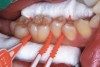

Interproximal insertion of SDF is demonstrated in different patients in Figure 3 through Figure 11. Various diameters and brands of soft dental picks may be used depending on the closeness of the proximal surfaces and ease of insertion; for example, some picks are designed for use in wider spaces between teeth. This protocol also offers versatility. Figure 3, for example, shows the simultaneous use of three thin soft dental picks to saturate proximal surfaces with SDF in a teenaged patient; the treated regions were subsequently covered with fluoride varnish (Figure 4). This patient was initially treated in April 2019 (Figure 5), with an identical re-application 3 months later. As shown in Figure 6, the December 2019 bitewing film revealed good results with the possible exception of the contact regions of the maxillary first and second molars. New SDF application was completed in the December appointment.

Figure 7 illustrates the use of thicker picks in premolar interproximal sites. Additionally, multiple picks can be used in one quadrant or in one proximal site with good isolation to maximize fluid saturation (Figure 9), which the authors have found to be an excellent time-saving strategy. Preventive or interceptive applications of SDF may also be effectively used in interproximal sites in orthodontic patients (Figure 10).

Fig 4. Three thin soft dental picks were used simultaneously for SDF proximal surface saturations in a teenaged patient (Fig 3). After 60 seconds, the treated regions were covered with 5% fluoride varnish (Fig 4). A comparison can be seen of pre-SDF-treatment bitewing films (Fig 5) and 8-month post-SDF bitewing films (Fig 6) for the patient shown in Fig 3 and Fig 4. Radiolucencies were similar or improved, except for contact of maxillary first and second molars.

Figure 4